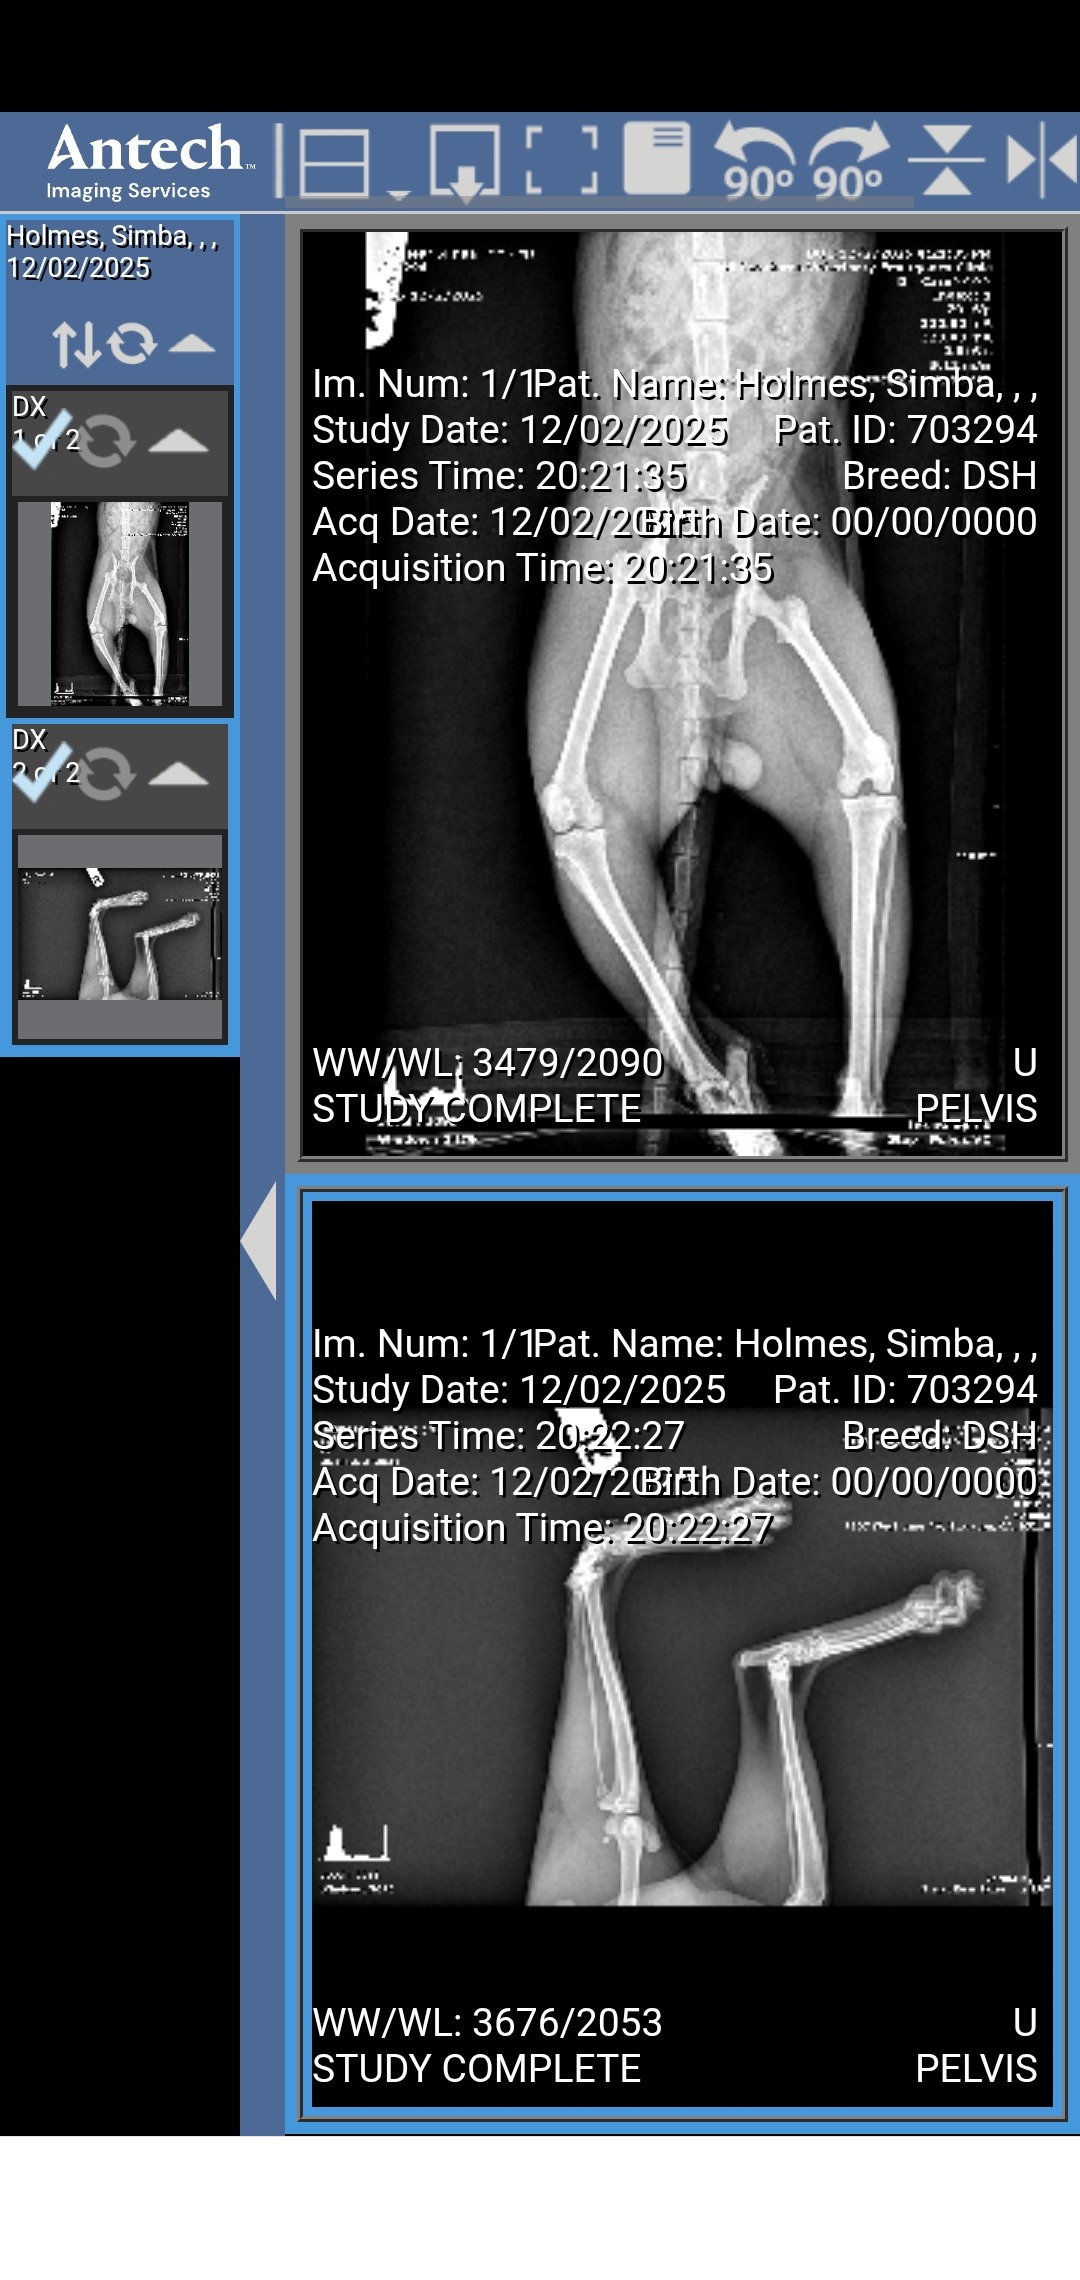

My name is Crystal. I'm desperately trying to get the money for surgery to amputate my kitty Simbas leg it would be $1500, I have $100 as of now. I don't have proof of the quote cuz it was over phone. He got out of the house yesterday and we think he'd been up in a car when it started and the belt mangled his leg and foot bad. Any help would be appreciated.